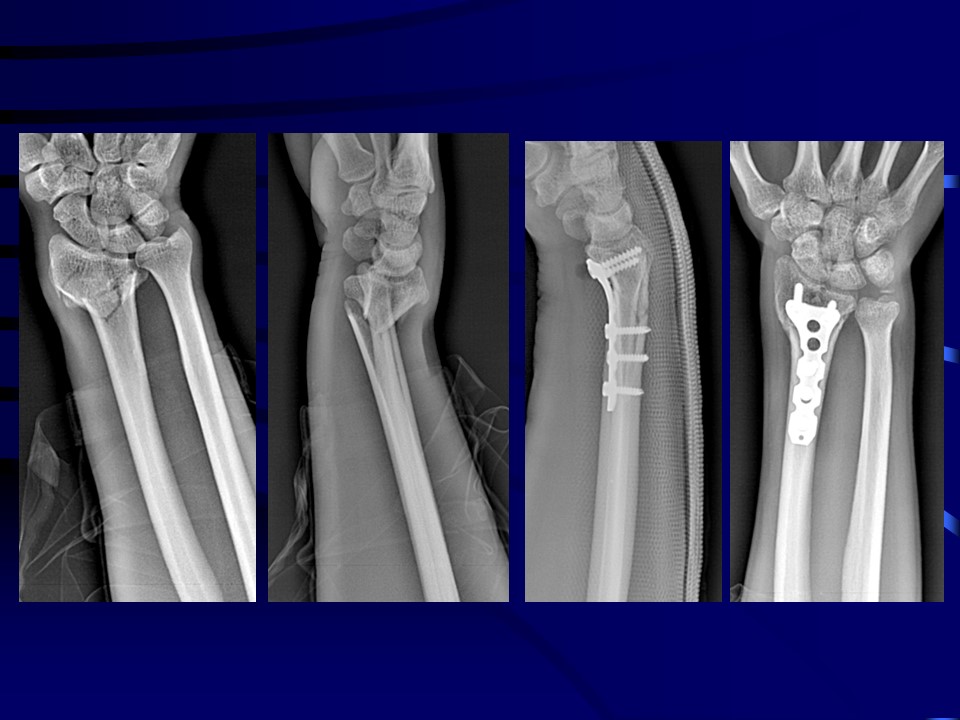

桡骨远端骨折治疗PPT

距桡骨远端关节面3cm内的骨 折,这个部位是松质骨和密质骨交界处,是解剖薄弱的 地方,容易发生骨折,其发生率约占急诊骨折病人 的1 7%。60---75岁高发,女性患者多于男性。